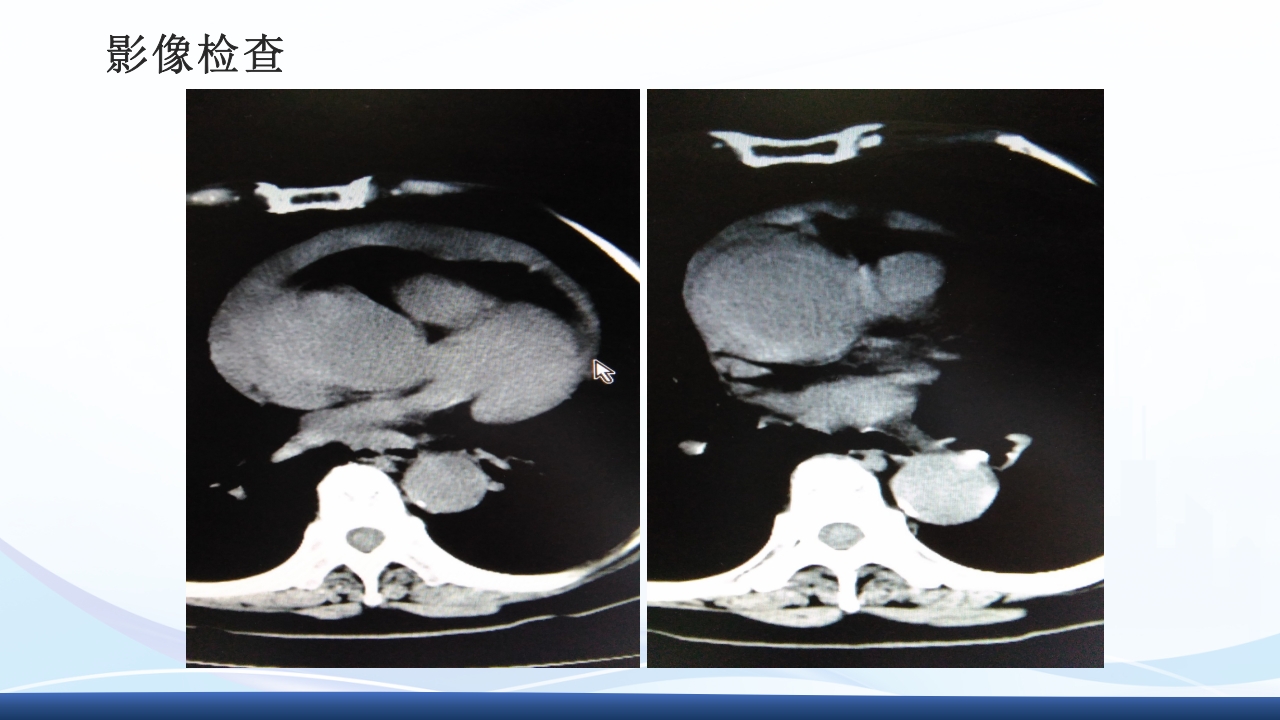

大纲 1 主动脉夹层的概念 2 病因与发病机制、分型 3 临床表现3 、辅助检查 4 主动脉夹层的诊断、治疗 5 病例介绍 64 护理诊断与措施、健康宣教 解剖图 解剖图 主动脉夹层的概述 主动脉夹层(aortic dissection AD)指主动脉壁中层 撕裂、分离,使主动脉壁内形成血肿,并沿纵向延伸。 AD最常发生在50-70岁的男性,男女性别比约2-5:1, 是与人类主动脉有关的最常见的死亡原因。 Thoraci caorta Abdomin alaorta Aortic dissection Aorta Blood in wall of artery Blood in artery 病因 结缔组织遗传缺陷性疾病:如马方(Marfan)综合征、埃-当(Ehlers-Danlos)综 合征、先天性主动脉缩窄、二叶主动脉瓣及二尖瓣脱垂等患者。 高血压:临床与动物实验发现,不是血压的高度...